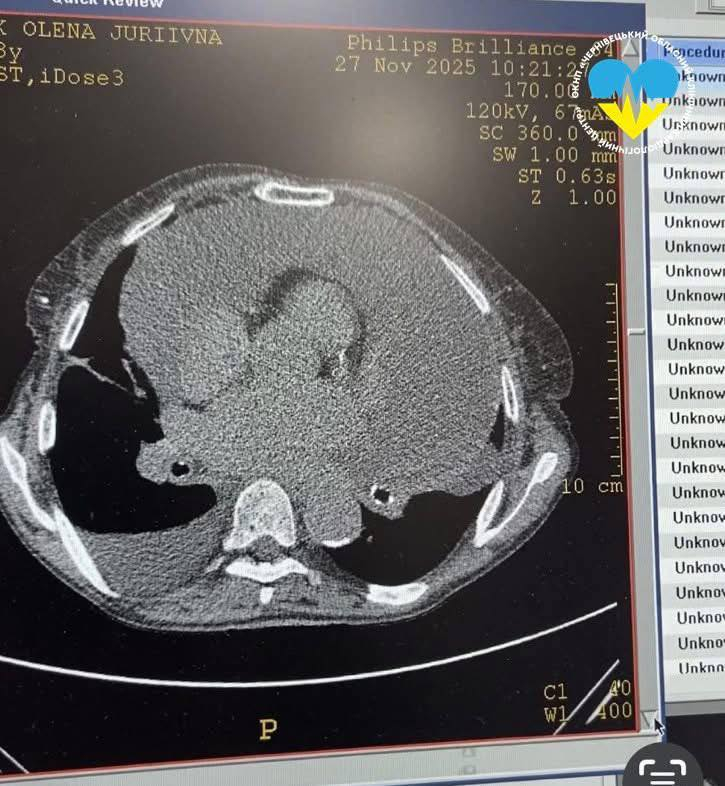

До Чернівецького обласного кардіоцентру доправили 78-річну жінку, яка скаржилася на сильну задуху протягом останніх двох місяців. Щоб встановити причину, пацієнтці провели комплексне обстеження: ехокардіографію, рентген та КТ органів грудної клітки.

Як зазначається, у результаті вдруге підтвердили діагноз гідроперикардиту – скупчення надлишкової рідини в перикарді. Чотири роки тому жінка вже перенесла операцію з її видалення в іншому медичному закладі.

Під час втручання з порожнини перикарда було видалено 2 літри 400 мл рідини. Після цього стан жінки значно покращився. Для контролю її здоров’я медики повторно провели ехокардіографію та комп’ютерну томографію, щоб оцінити стан перикарда та з’ясувати причину виникнення небезпечної ситуації.